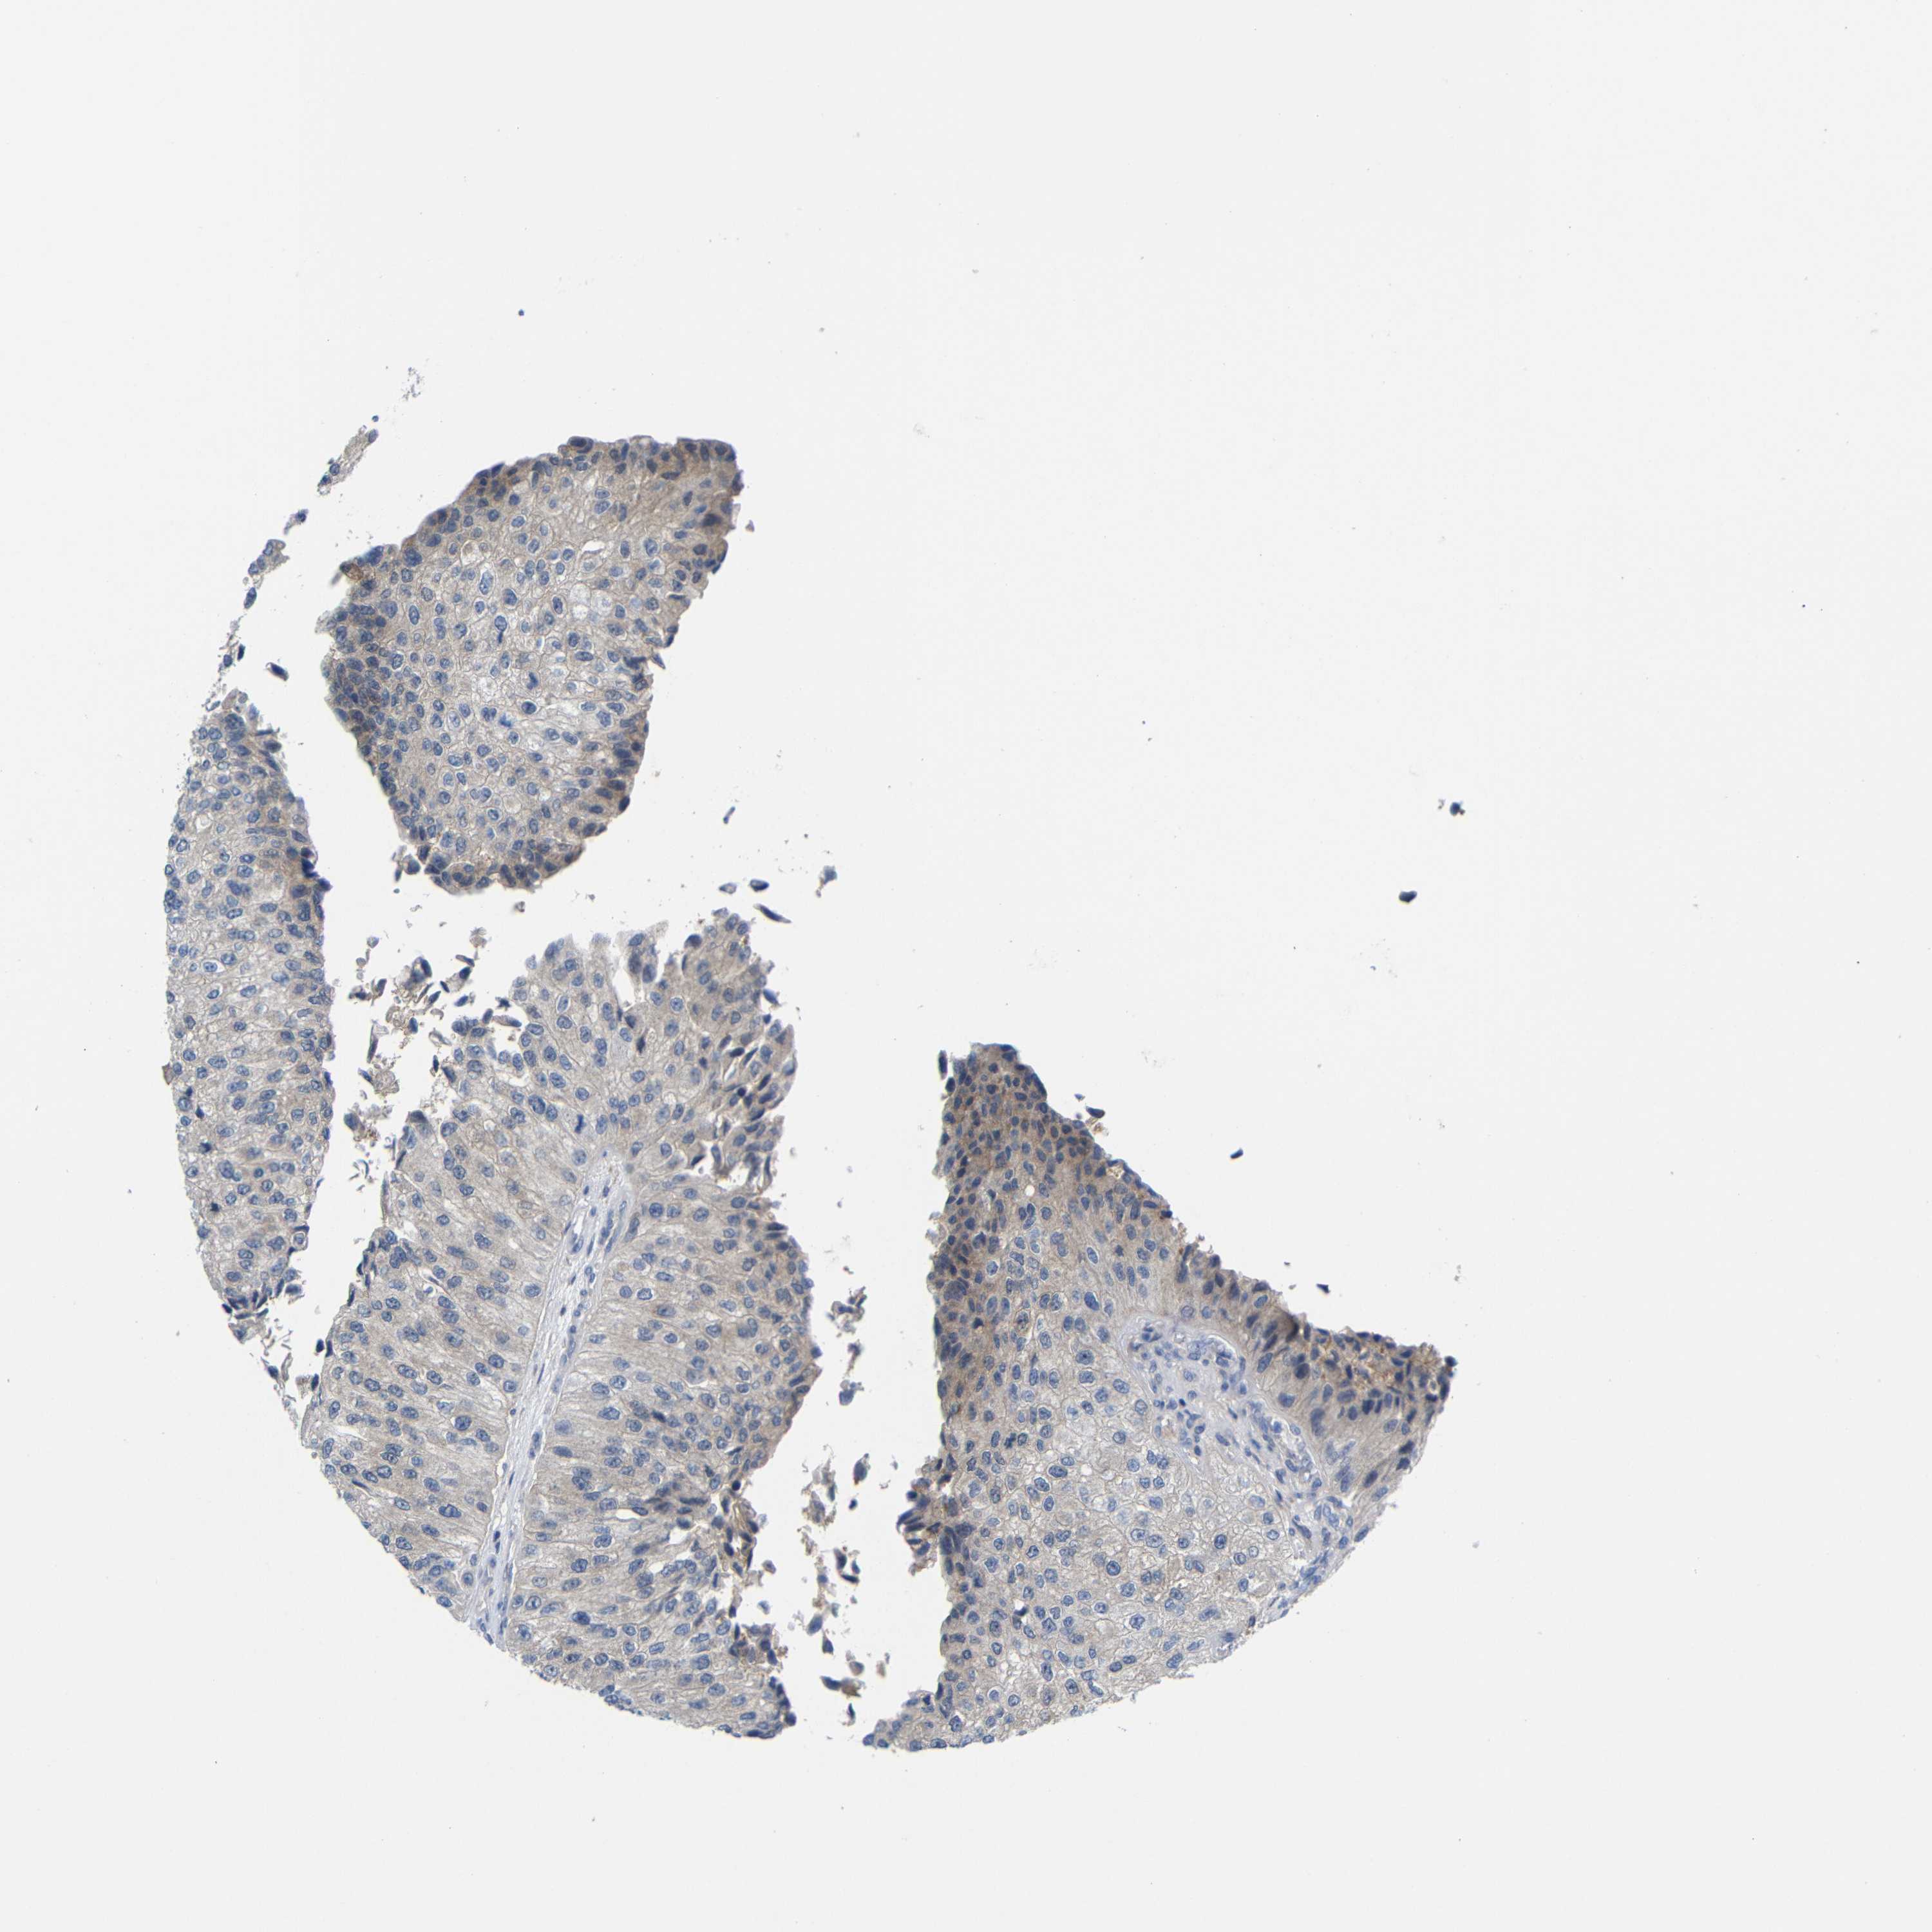

UROTHELIAL CANCER - Protein expressioni

A mouse-over function shows sample information and annotation data. Click on an image to view it in a full screen mode. Samples can be filtered based on level of antibody staining by selecting one or several of the following categories: high, medium, low and not detected. The assay and annotation is described here.

Note that samples used for immunohistochemistry by the Human Protein Atlas do not correspond to samples in the TCGA dataset.

Antibody stainingi

Antibody staining in the annotated cell types in the current human tissue is reported as not detected, low, medium, or high, based on conventional immunohistochemistry profiling in selected tissues. This score is based on the combination of the staining intensity and fraction of stained cells.

Each image is clickable and will lead to virtual microscopy that enables deeper exploration of all samples and also displays staining intensity scores, fraction scores and subcellular localization as well as patient and tissue information for each sample.

Antibody CAB013493

Urothelial carcinoma, Low grade